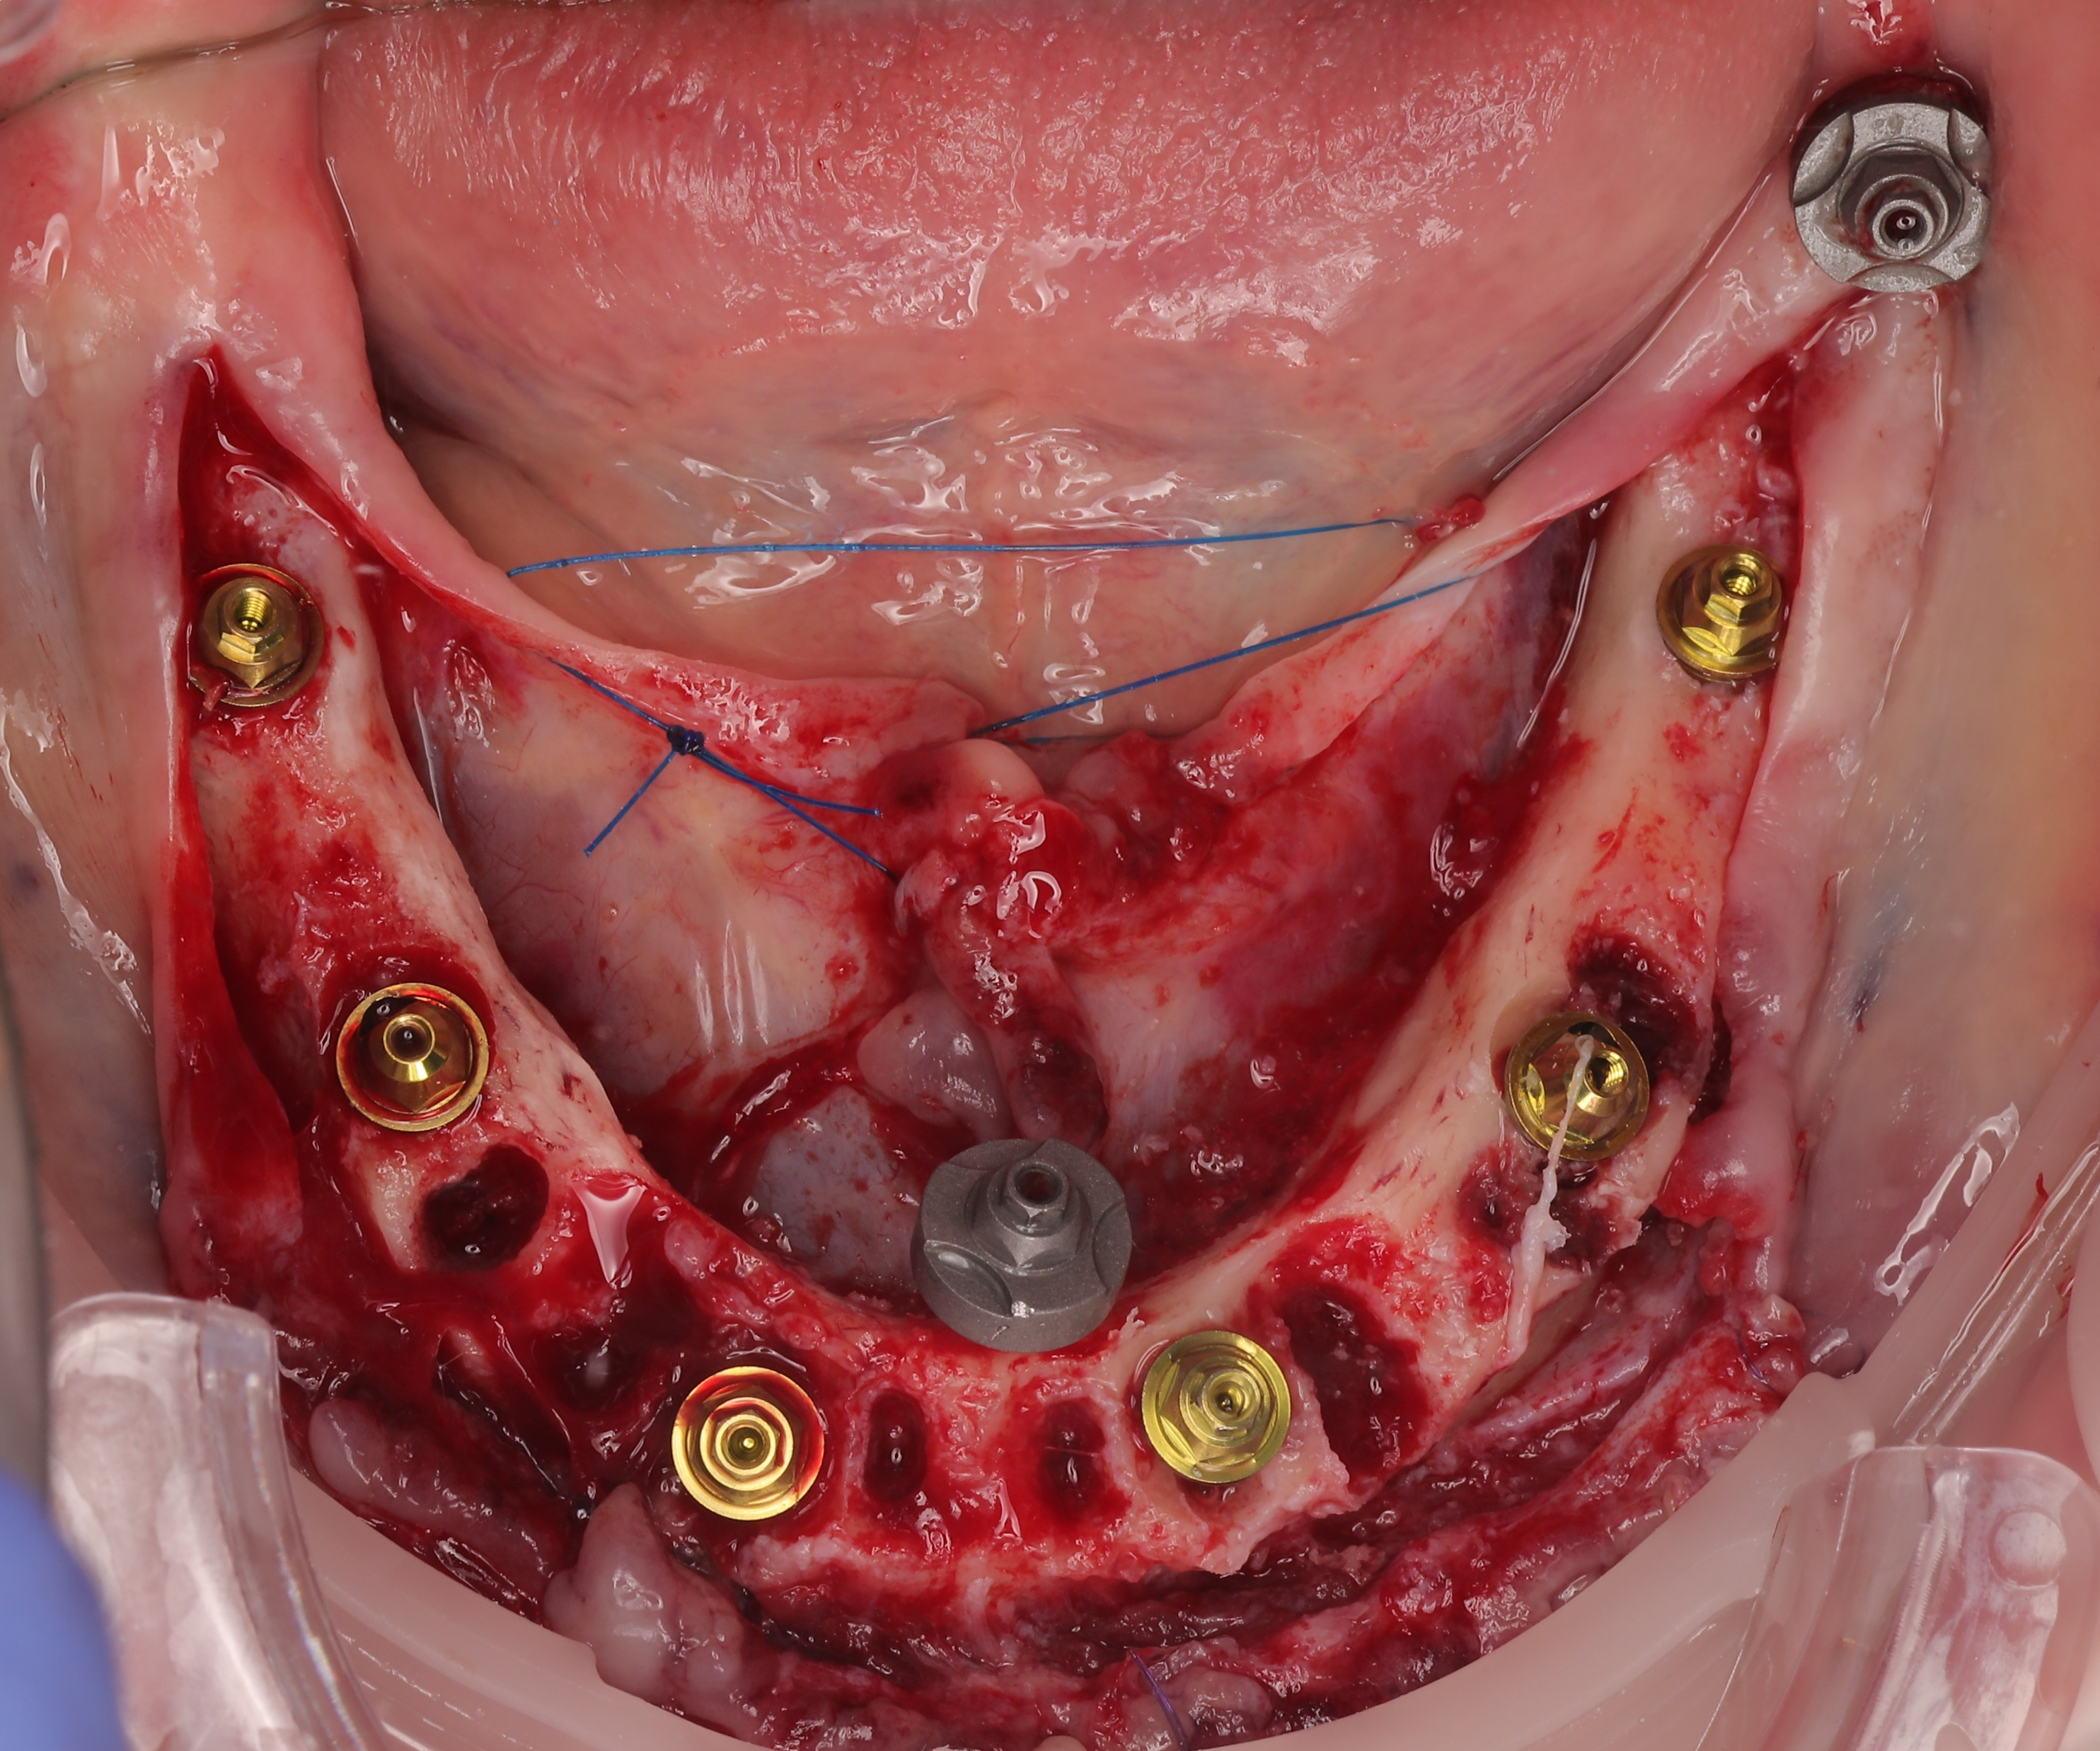

Maxillary :

The surgical phase began with the placement of palatal scan markers for digital alignment, followed by a full-thickness flap elevation. To maintain the buccal ridge profile, the Root Shield technique was performed at sites 13, 12, and 23, where vestibular bone support was sufficient. JDental Icon Plus implants were installed in the remaining sites. To address posterior bone deficiency without sinus augmentation, JDental Paga3 pterygoid implants were placed via a transsinusal approach. The workflow concluded with soft tissue management, forming a critical step in the overall digital dental workflow for full arch dental implants rehabilitation.

Mandibular :

Following marker placement and necessary bone reduction, JDental Icon Plus implants were installed and fitted with Multi-Unit Abutments (MUA). A preliminary suturing was performed to stabilize the site, after which a mandibular IPG scan was executed to capture precise implant positions. The procedure was finalized with the complete closure and suturing of the gingival grafts to ensure optimal soft tissue healing.